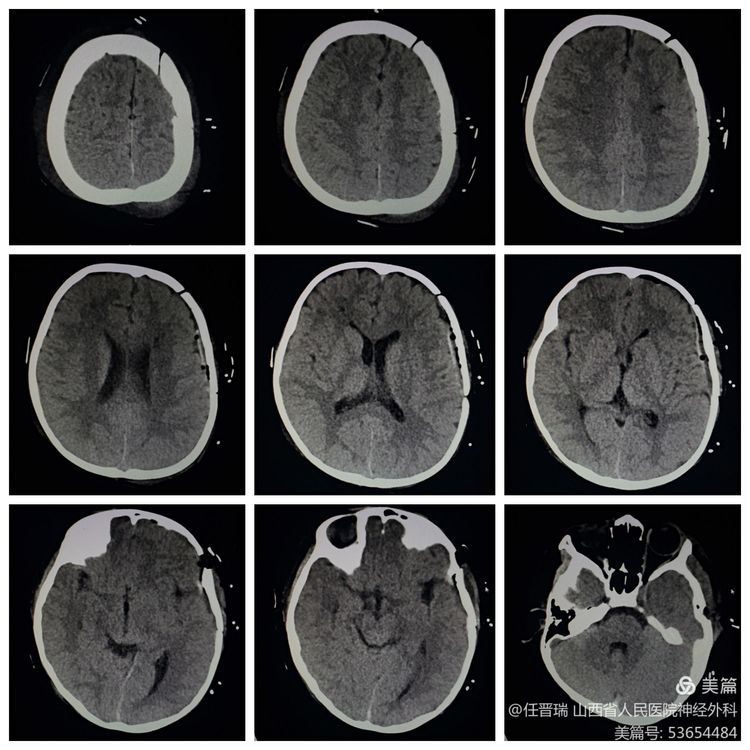

入院3月前颅脑MR: 双侧额顶叶可见多发急性脑梗死灶

3月前颅脑MRA:双侧大脑中动脉闭塞及双侧大脑前动脉闭塞

入院前CT:经治疗脑梗死好转,左侧额叶脑内软化灶形成

术前MR:未见新发脑梗死

术前CTP:双侧额叶低灌注

全脑血管造影:双侧大脑中动脉及双侧大脑前动脉闭塞,颈内动脉末端烟雾样血管形成

入院诊断: 烟雾病 陈旧性脑梗死

术后复查颅脑CT术区未见出血及梗死灶